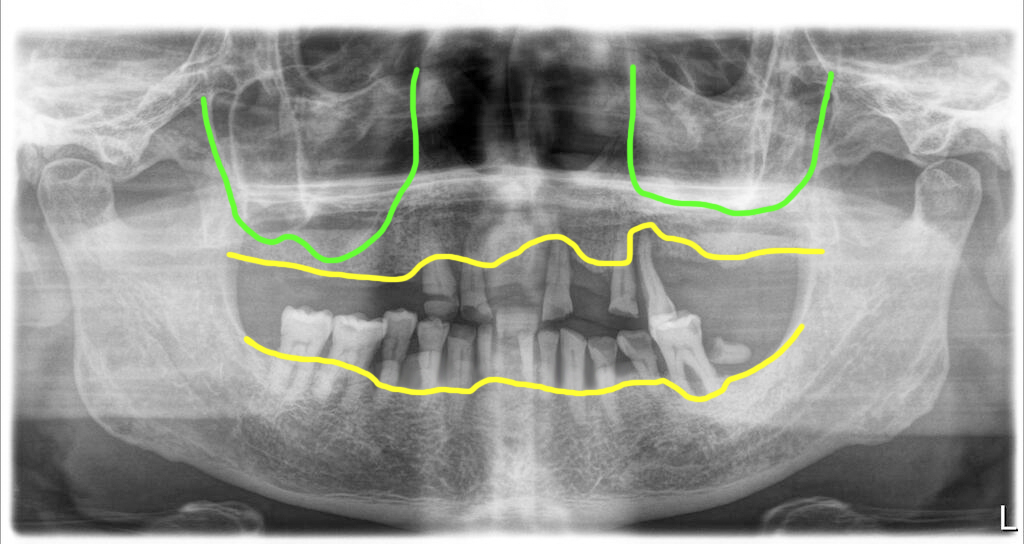

다수의 치아상실과 치아마모 그리고 치주염으로 흔들리는 치아들

치아가 여러개 빠졌지만 치료를 하지 않고 방치한 상태였습니다. 위쪽은 거의 대부분의 치아가 빠져 있었고, 앞니 부분에 몇 개의 치아가 남아있었지만 앞니로 계속해서 식사를 한 탓인지 결국 그 치아들도 많이 흔들리고 치주염이 많이 진행이 되어 있었습니다.

아래턱에는 그래도 치아들이 꽤 남아 있었습니다. 그러나 남아있는 치아들의 치주상태가 좋지 않고 마모상태가 심해서 장기적으로 견디기 힘들다고 판단되는 치아들은 제거하기로 했습니다. 우측의 어금니 2개는 상태가 양호해서 남기기로 했구요.